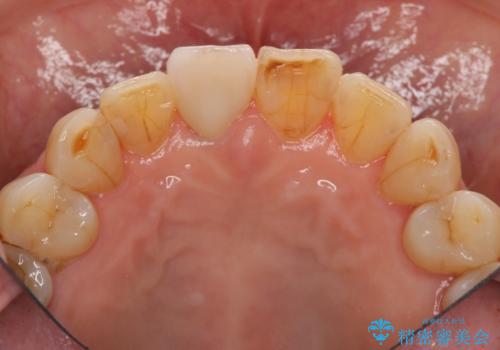

天然歯を模した ハイグレードオールセラミッククラウン

当法人でご提案できる最上位クラスのジルコニアクラウンです。

透明感や周囲の歯との色の調和に大変ご満足いただけました。